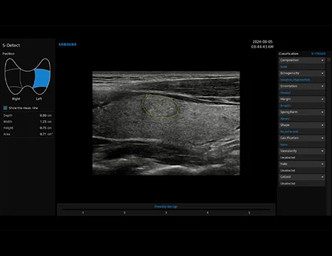

Teşhis ve raporlamayı kolaylaştırmak için seçilen tiroid lezyonlarını analiz eder ve ölçer.